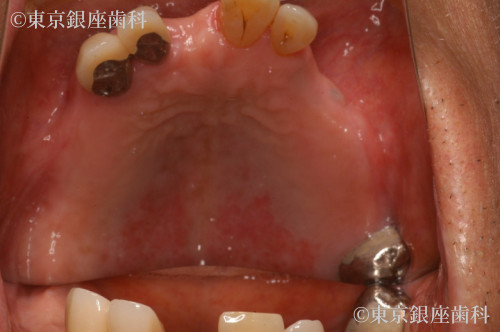

重度歯周病、義歯不適合による咬合障害をワンデイインプラントで改善した症例

Before

全体的に歯周病が進行していること、咬合改善を希望されていることから残存歯を全て抜歯してワンデイインプラントにすることにした。

ご高齢の為術前、術後の全身管理を徹底しました。また、喫煙は術後の治癒の遅延やインプラントと骨の結合阻害等のリスクがあるため、

減煙していただいてから手術を行いました。